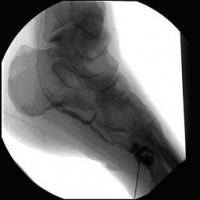

Perkutane Embolisation einer low-flow venösen Malformation (Gefäßmissbildung) der Fußsohle-1

(Bild 4 von 5)

Perkutane Embolisation einer low-flow venösen Malformation (Gefäßmissbildung) der Fußsohle-2

(Bild 5 von 5)